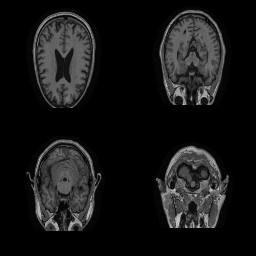

| Original | Renderings after de-identification | Original | MRI slices after de-identification | ||||||

| CP-GAN | FACE MASK | DEFACE | QUICKSHEAR | CP-GAN | FACE MASK | DEFACE | QUICKSHEAR | ||

Benchmark De-Identification Methods. We compare our result with three publicly available and widely-established methods for de-identification of MRI head scans, depicted in Figure 3. All methods have in common that they (1) are not deep-learning-driven, (2) require no additional training and (3), are used on a day-to-day basis in neuroscience and clinical research. All procedures were applied with default settings on images of resolution . The methods include QUICKSHEAR [Schimke et al.(2011)Schimke, Kuehler, and Hale], FACE MASK [Milchenko and Marcus(2013)], and DEFACE [Bischoff-Grethe et al.(2007)Bischoff-Grethe, Ozyurt, Busa, Quinn, Fennema-Notestine, Clark, Morris, Bondi, Jernigan, Dale, Brown, and Fischl]. Descriptions of the methods are provided in the Appendix. We also include MRI WATERSHED [Ségonne et al.(2004)Ségonne, Dale, Busa, Glessner, Salat, Hahn, and Fischl], a skull-stripping method that removes everything except the brain.